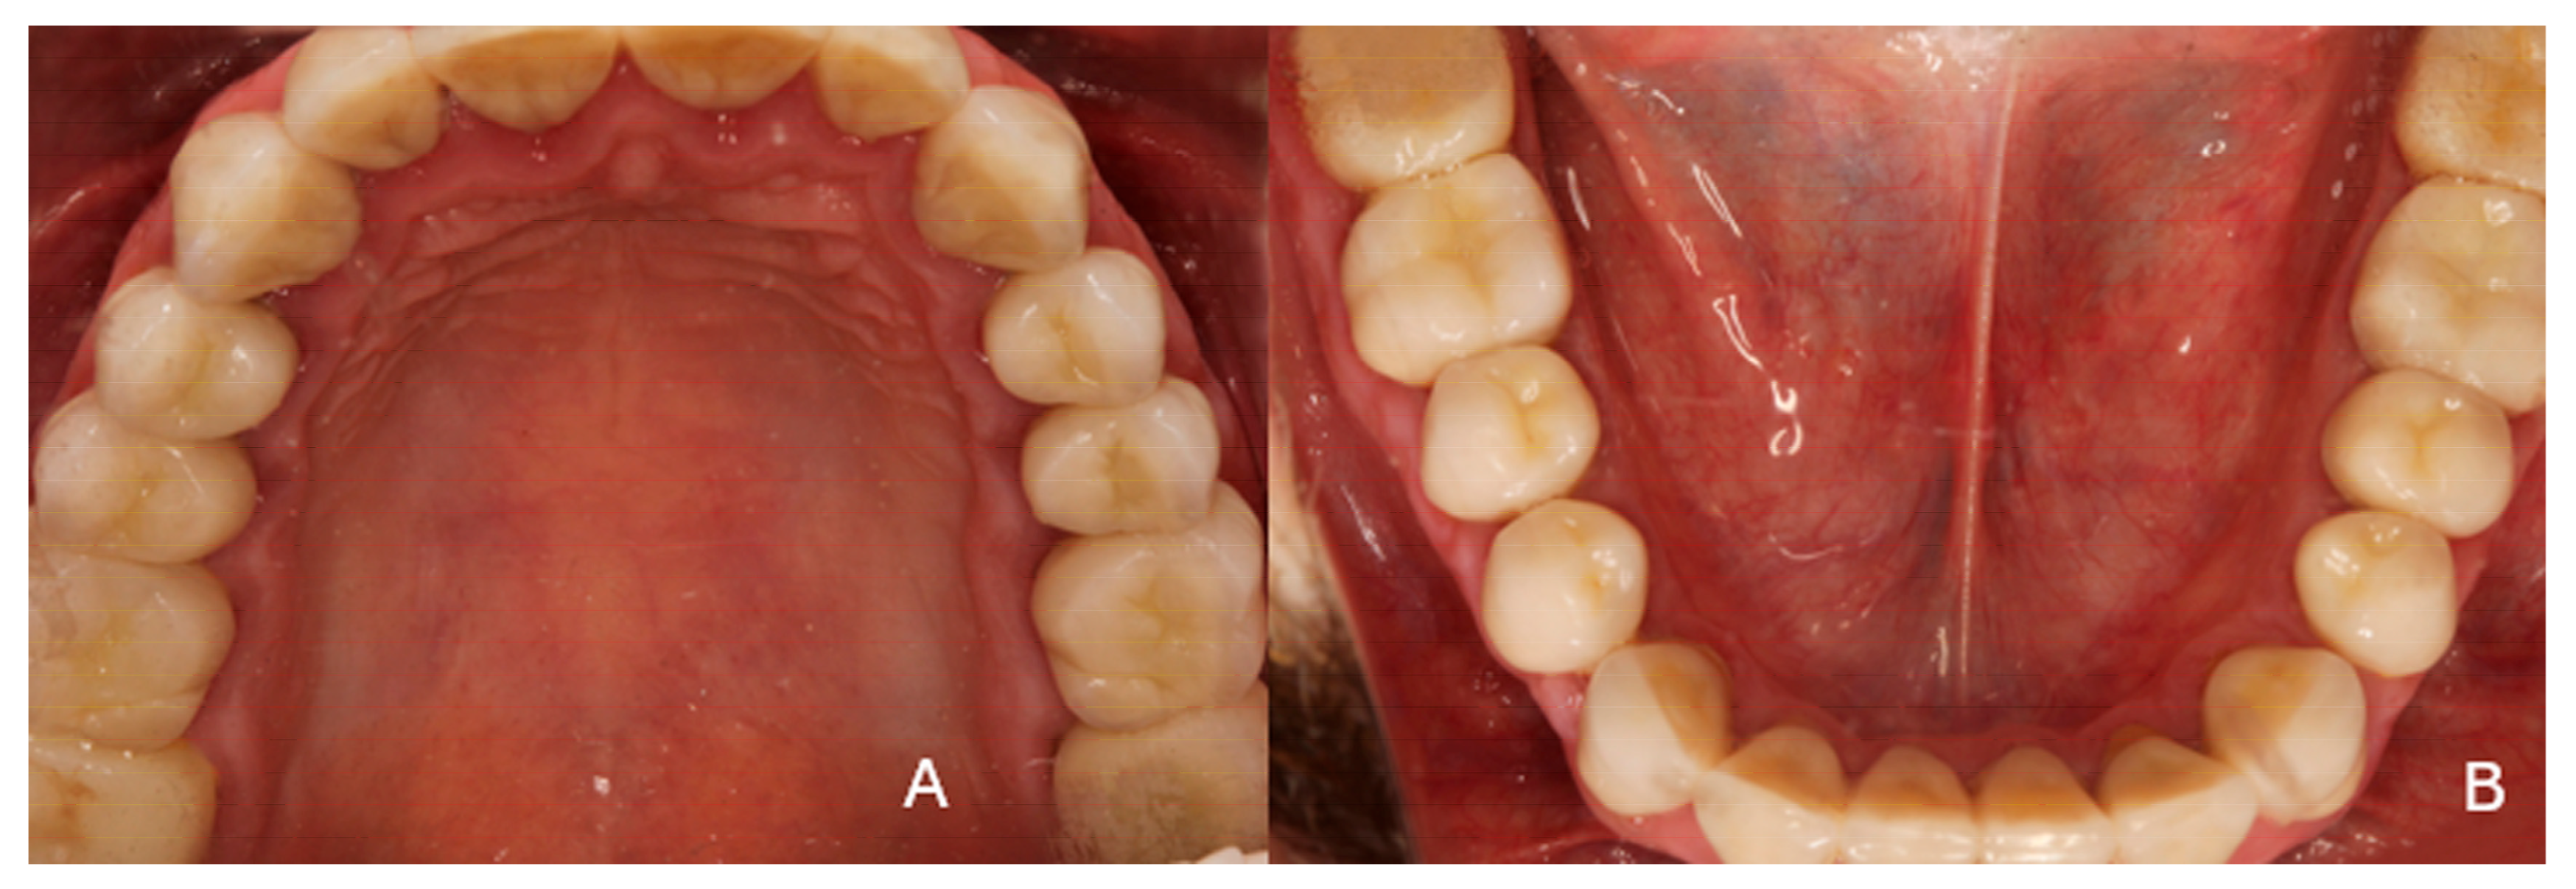

2. Case Presentation